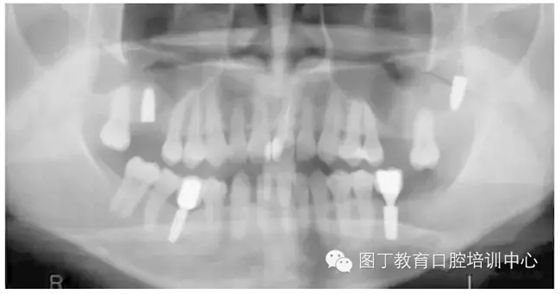

臨床上,可使用曲面體層放射線法及CT掃描方法對(duì)上額竇及可用骨量進(jìn)行評(píng)估。其中曲面體層放射線法可提供多數(shù)病例的硬腭致密影像,為治療計(jì)劃提供有價(jià)值的參考(圖1);而使用CT掃描可提供骨密度信息。如骨高度、密度、牙槽嵴的方向位置,皮質(zhì)骨和松質(zhì)骨的特點(diǎn),上頜竇黏膜厚度,病理狀態(tài)等。顯然,在上頜竇底提升術(shù)中,CT掃描影像的信息對(duì)于手術(shù)設(shè)計(jì)和減少治療風(fēng)險(xiǎn)非常重要。

圖1 采用曲面體層放射線法評(píng)估